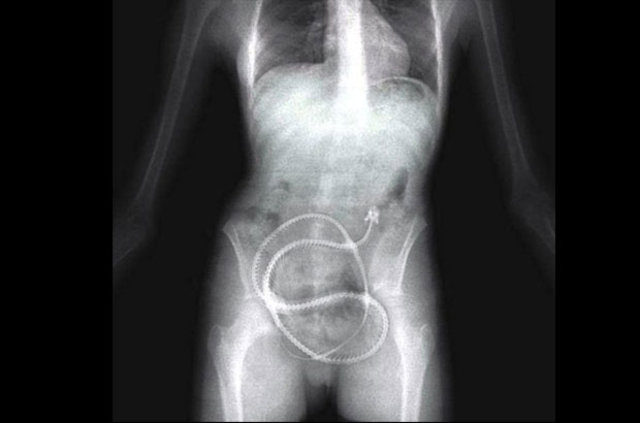

İzmir'deki Tepecik Eğitim ve Araştırma Hastanesi Çocuk Gastroenteroloji Bölümü'nün, yabancı cisim yutan çocukların nefes ve borusu ile midelerinden çıkarttığı, anahtarlık, madeni para, saat pili, ataç, çengelli iğne ve çivi gibi objeler görenleri şaşkına çevirdi.

Çocukların nefes ve borusu ile midelerinden çıkartılan, anahtarlık, madeni para, saat pili, ataç, çengelli iğne ve çivi gibi objeler görenleri şaşkına çevirdi. Anne ve babaların çok dikkatli olması gerektiğini söyleyen Doç. Dr. Maşallah Baran, şöyle dedi:

Genellikle yabancı cisimler 'X' ışınıyla görülebilir. Direk grafi ile metal ve 'X' ışınına duyarlı cisimleri rahatlıkla görebiliyoruz. Ama plastikleri göremiyoruz. Bu durumda oyuncağın bir parçasıyla yutulan parçayı anlamaya çalışıyoruz."